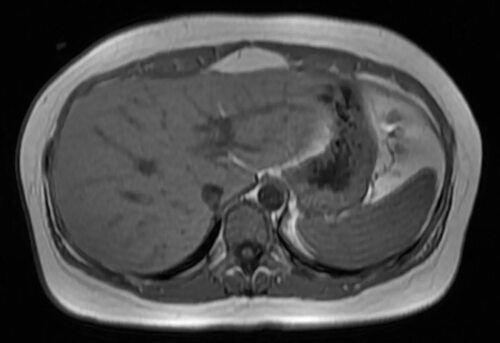

Фото МРТ печени

Ниже приведены некоторые фотографии, полученные с помощью МРТ печени. Изображения позволяют увидеть различные структуры, текстуры и изменения, которые могут быть связаны с разными заболеваниями печени.

Важно отметить, что эти фотографии предоставляются исключительно для информационных целей и не заменяют консультацию с врачом. Точное понимание и диагностика возможных патологий печени может быть осуществлена только квалифицированным специалистом.